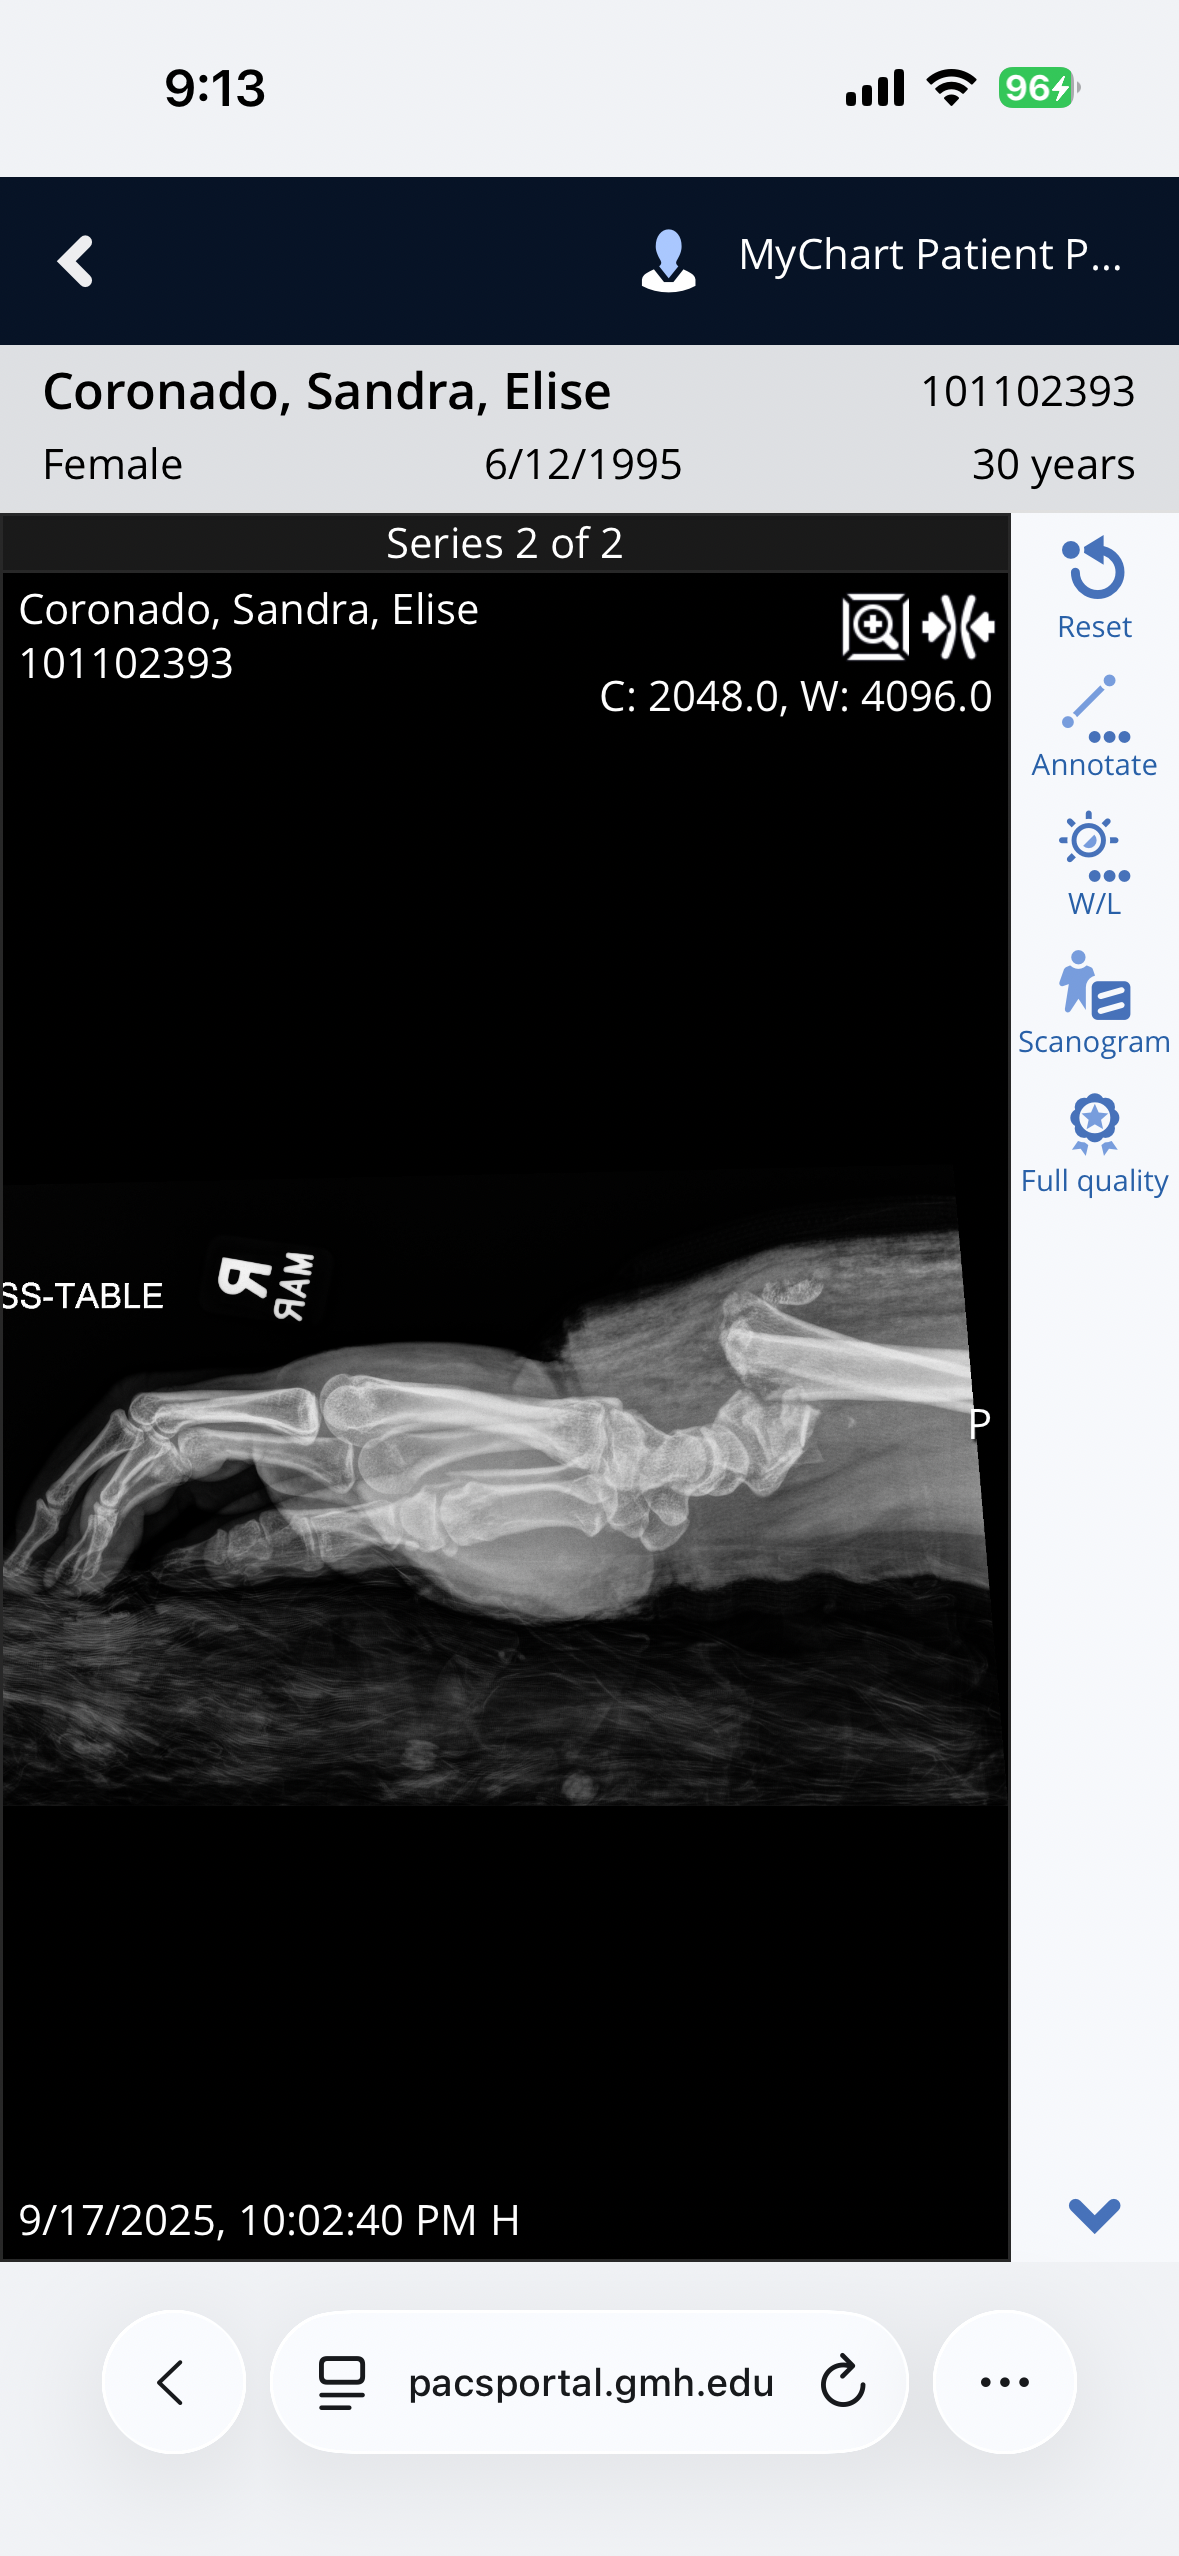

Hi, my name is Sandra I am 30 years old and I got into a motorcycle accident on September 17th. I was going the speed limit, I had the right way, and a woman pulled out in front of me trying to get to the median. I hit her driver side front tire at about 40 to 45 mph. I flew over her car and landed and slid. I was awake through the whole thing. I shattered my right ankle and broke my right tibia. My left ACL was tore and I broke a bone in my left knee. My right wrist was shattered and I have a couple of bones broken in my hand, my left elbow was dislocated. Ligaments were torn and a bone is broken. I can’t walk and I can’t use my arms for anything. I have fallen through all of the medical cracks for my insurance to cover what I need. I have a lot more cost than what I’m asking for but honestly anything helps. I’m going to need someone to care for me while my husband is at work. The doctors estimate about three months before I can even start rehabilitation therapy. I still have another surgery on my right leg and my left leg. My insurance does not cover in-home care and my insurance won’t cover the rehabilitation therapy. I used to work three jobs, two of which required very detailed work with my hands and sadly I’m not sure if I’ll ever be able to do that again. The doctor also mentioned that I may never have full function of my right hand or my right leg due to bones being shattered and broken in the manner that they were.